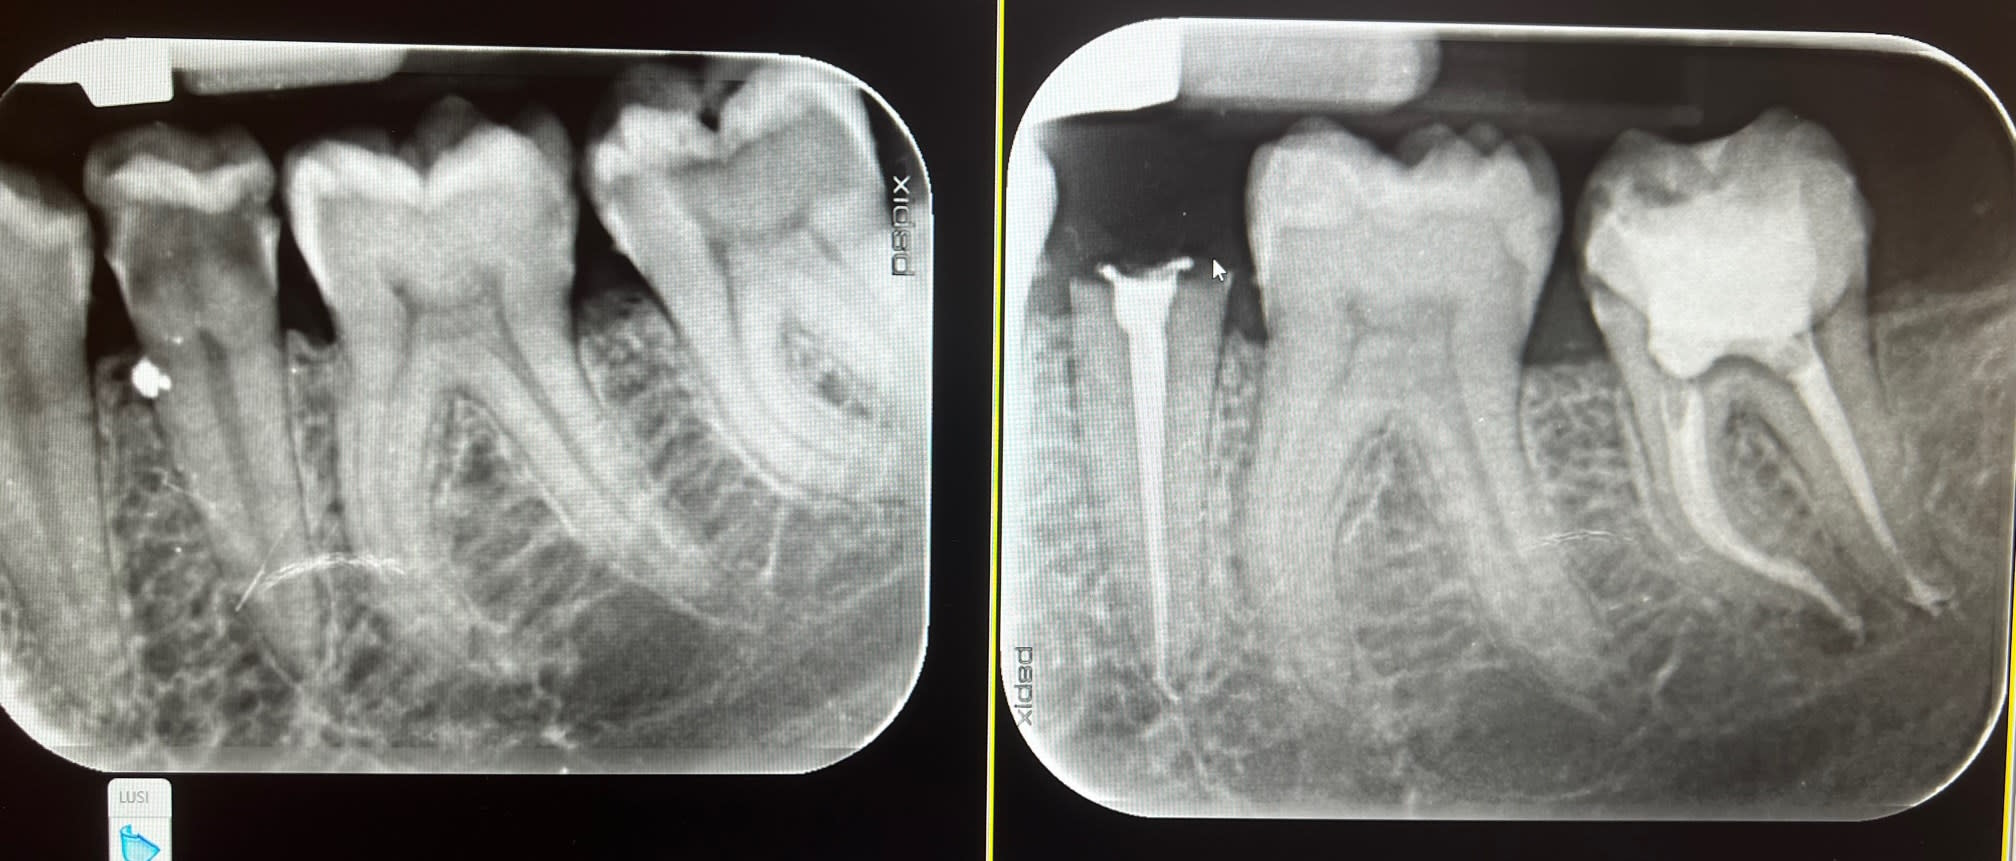

Je couronne pas toutes les dents dépulpées que je vois , si il y en a le besoin je reprends l'endo quand j'ai une image à l'apex , autrement je le fais pas si radiographiquement tout va bien. Et pour ce qui est du spé endo bah écoute le plus proche il est à 200km de mon cabinet donc comment te dire qu'on fais en sorte de pas en avoir besoin.

Mes endos sont sous digue, peut être pas digne d'un spé endo mais j'en suis satisfait

C'est juste du travail normal et un cas simple quelques endos et couronnes. Ca n'a rien d'un plan de tt global multi disciplinaire. ( ortho, paro occluso.....)